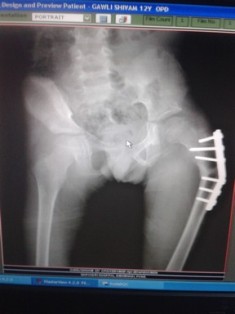

Best Scissoring Treatment In Pune

Radiograph of hip showing dislocation of left hip